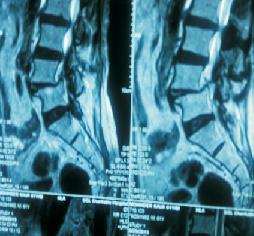

Large Intradural Dermoid